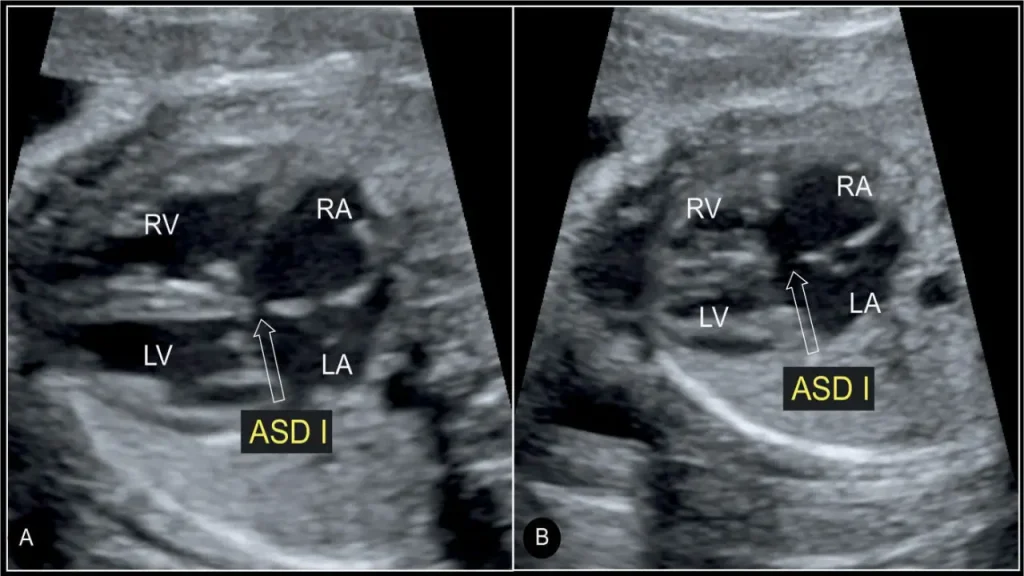

اکو قلب جنین یا Fetal Echocardiography نوعی سونوگرافی تخصصی است که به پزشکان امکان میدهد ساختار و عملکرد قلب جنین را در دوران بارداری با دقت بالا بررسی کنند. در این روش، دستگاههای پیشرفته با استفاده از امواج فراصوت تصویری دقیق از قلب، بطنها، دهلیزها، دریچهها، عروق اصلی و حتی ریتم قلب جنین ایجاد میکنند. به همین دلیل، اکو قلب جنین یکی از ابزارهای حیاتی برای تشخیص زودهنگام مشکلات قلبی محسوب میشود.

هدف اصلی از انجام این بررسی، تشخیص ناهنجاریهای مادرزادی قلب قبل از تولد است. بسیاری از مشکلات قلبی اگر در همان دوران جنینی شناسایی شوند، میتوانند با برنامهریزی مناسب بعد از تولد یا حتی در برخی موارد در دوران بارداری مدیریت شوند. برای مثال، اگر نقص ساختاری قلب یا اختلال در جریان خون مشاهده شود، پزشکان میتوانند اقدامات لازم مانند مشاوره ژنتیک، ارجاع به فوقتخصص قلب کودکان یا برنامهریزی برای تولد در مرکز مجهز را در نظر بگیرند.

- یافتههای غیرطبیعی در سونوگرافی آناتومی: هر گونه انحراف در اندازه قلب، عروق یا ریتم میتواند نشانهای برای بررسی دقیقتر باشد.

- کیفیت تجهیزات: دستگاههای پیشرفته با قابلیت Doppler و تصویربرداری سهبعدی دقت تشخیص را بسیار افزایش میدهند. به همین دلیل مراجعه به بهترین مراکز اکو قلب جنین اهمیت زیادی دارد.